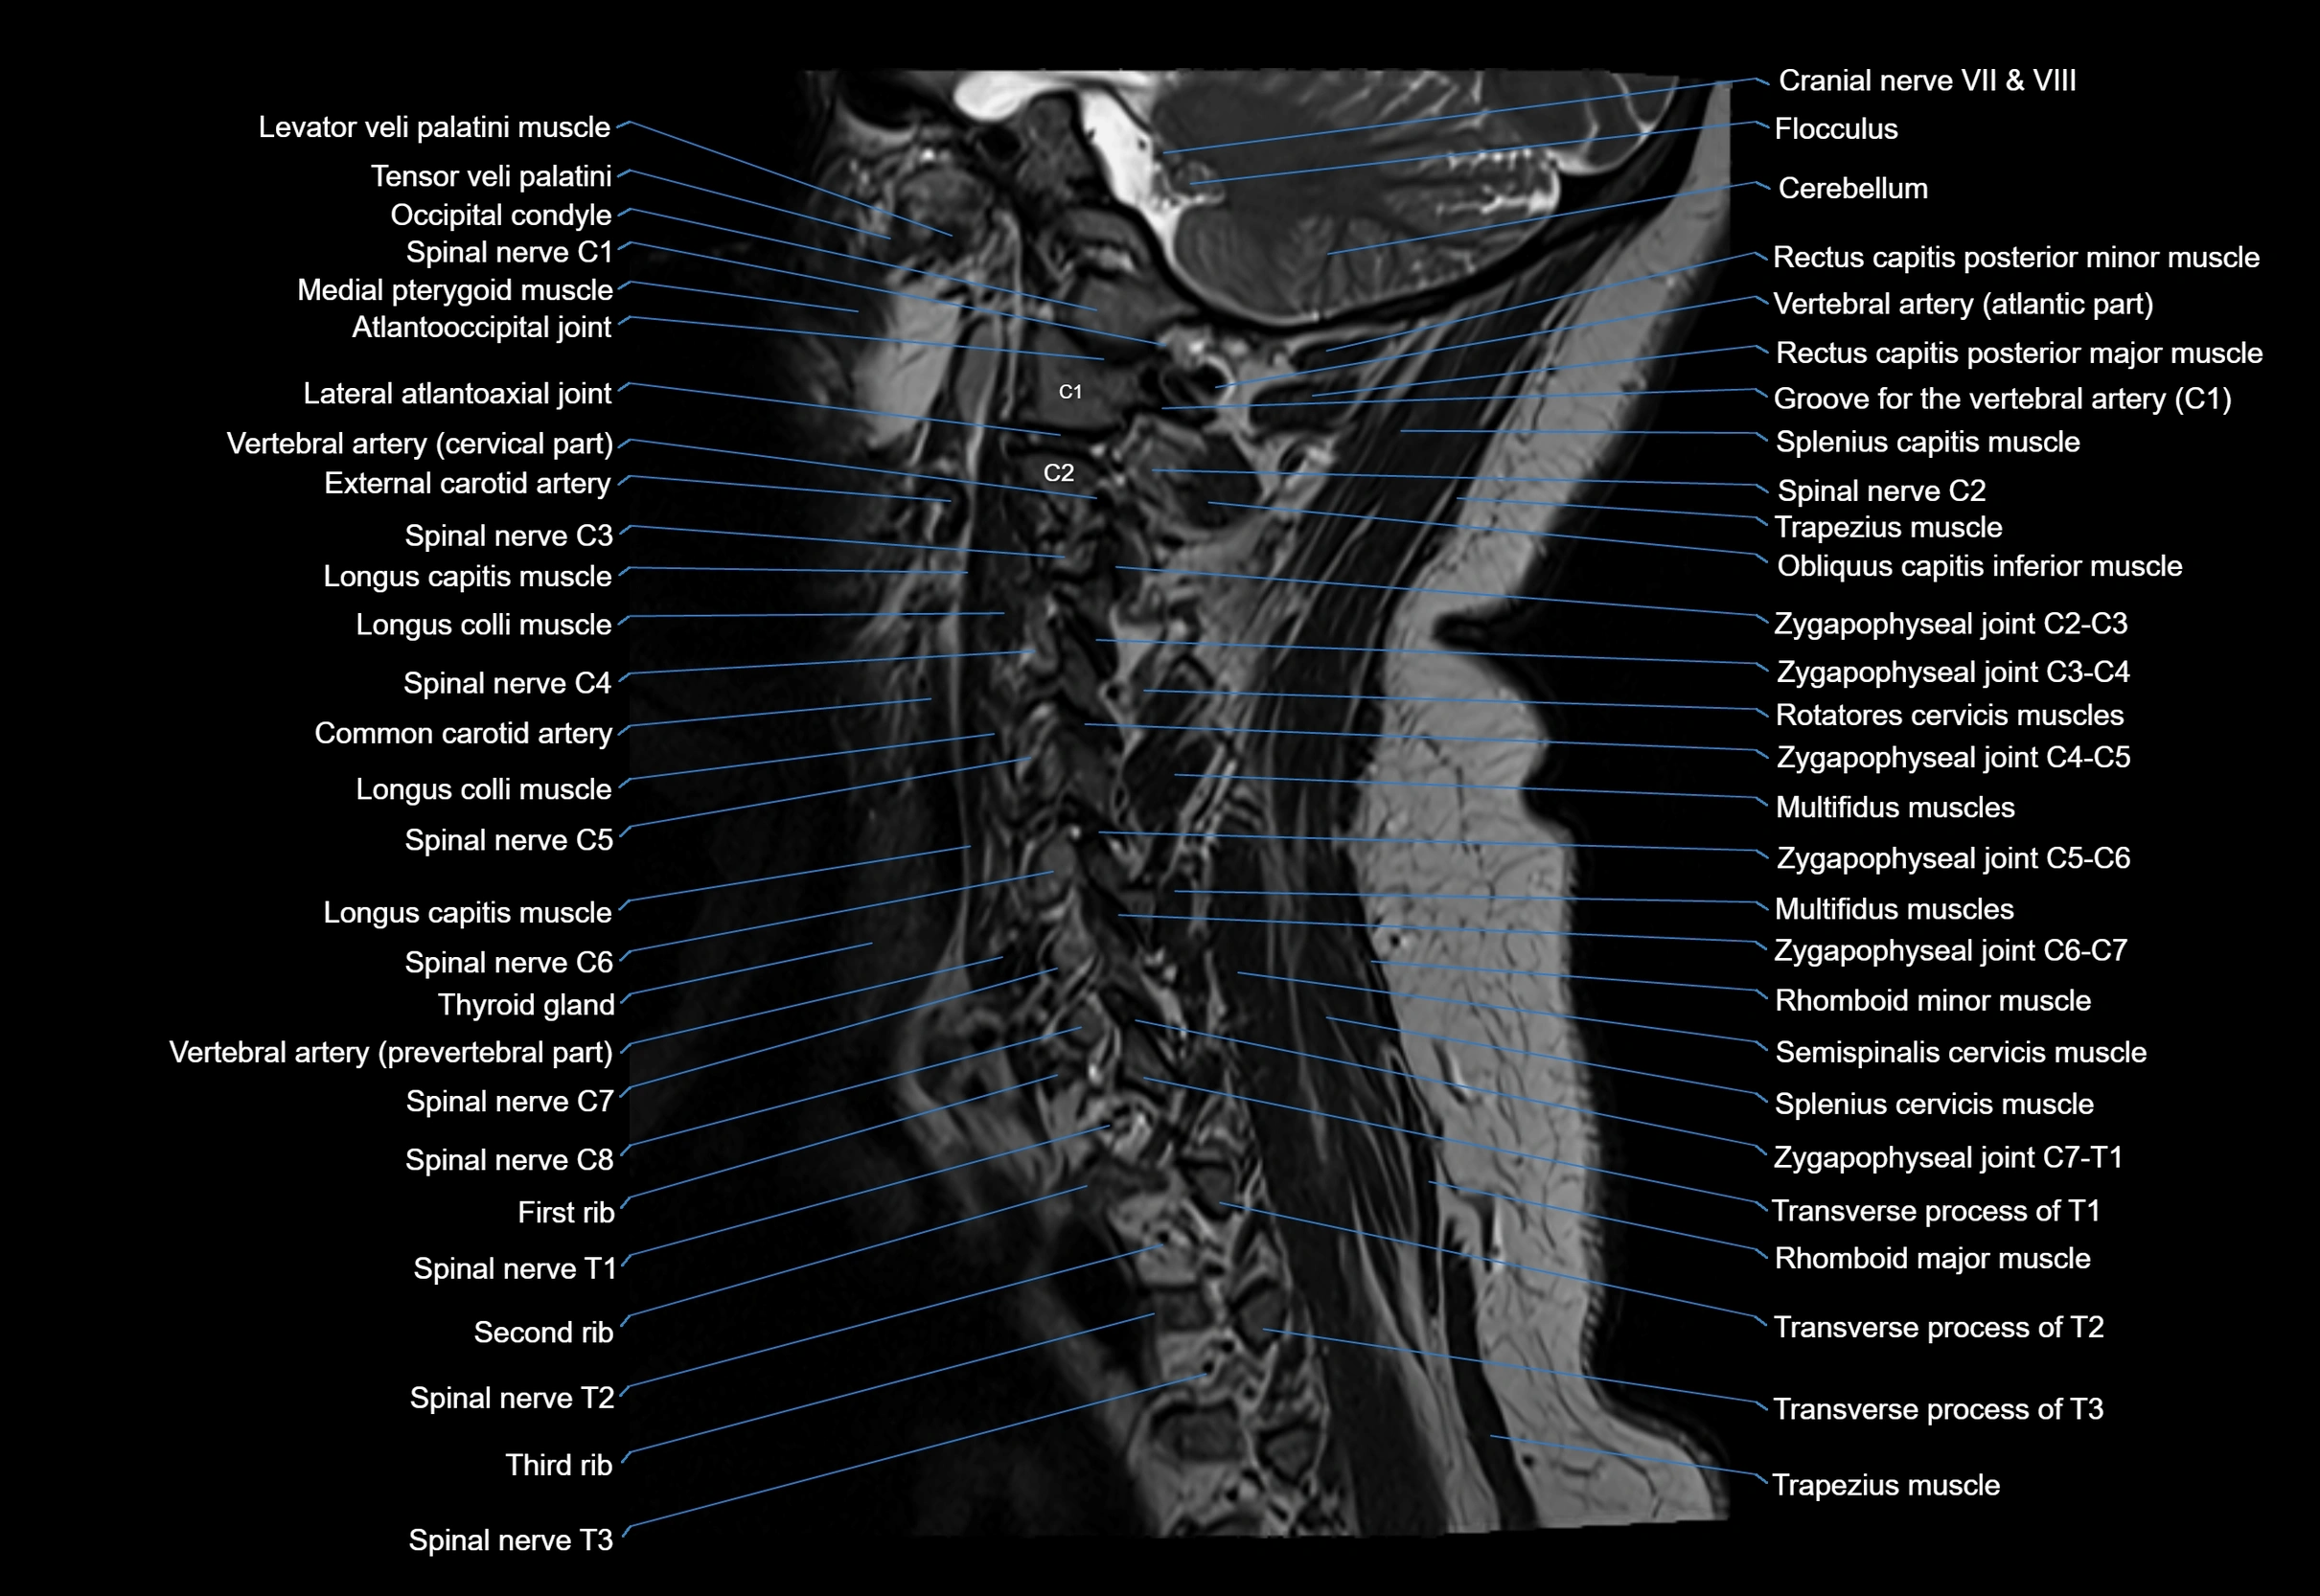

MRI image

image